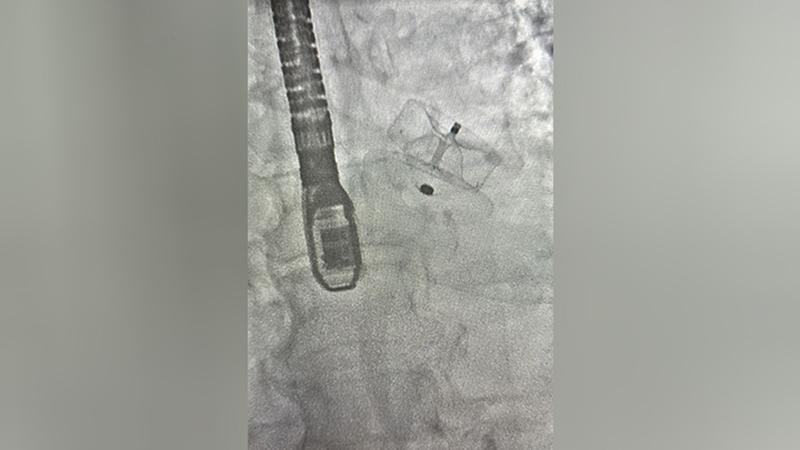

В Мариинской больнице Петербурга впервые провели операцию по окклюзии ушка левого предсердия. Об этом сообщили в пресс-службе городской больницы.

Бригада хирургов во главе с заведующим отделением рентгенхирургических методов диагностики и лечения, сердечно-сосудистым хирургом Вячеславом Зелениным, провела первую подобную операцию.

Профилактическое мероприятие для предотвращения тромбоэмболии у пациента с фибрилляцией предсердий успешно завершено. Сейчас пациент находится в терапевтической реанимации, его состояние стабильно и не вызывает опасений. Врачи высоко оценили точность процедуры и её первоначальные положительные эффекты. Это вмешательство расширяет возможности кардиологической помощи в клинике, позволяя проводить больше малоинвазивных операций пациентам с повышенным риском тромбоза. В скором времени проведут ещё две подобные операции, что говорит о готовности больницы к регулярному проведению таких процедур и внедрению этой передовой методики.